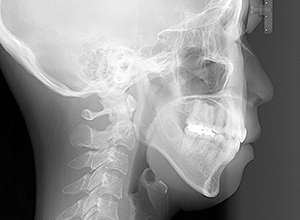

| 顔貌所見 | 顔面高は高く、面長で頤は尖っていた。オトガイは後退した印象があり側貌はconvex type、口唇閉鎖不全が認められた。 |

| セファロ所見 | Sellaから下顎頭までの距離は短く、骨体部は大きいが下顎枝の長さが短く、下顎角は開大しているためハイアングルを呈していた。中顔面部の高さは高いため下顎はクロックワイズローテーションをしており前後的にはII級の骨格形態を示していた。 |

| 批評・予后 | 治療後において下顎角の開大も認められず歯軸の整直、咬合の緊密化が得られた。また上下顎前歯の後退と共に口元の突出感と口唇閉鎖不全の改善が認められた。 |